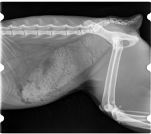

radiographie de gestation chienne

Dépistage officiel de la dysplasie de la hanche et du coude.

Radiographie de gestation

Nous disposons d'un équipement de radiologie numérique.

Les radiographies sont d'un atout majeur dans le diagnostic de nombreuses pathologies (fractures, problèmes respiratoires, troubles digestifs ...).